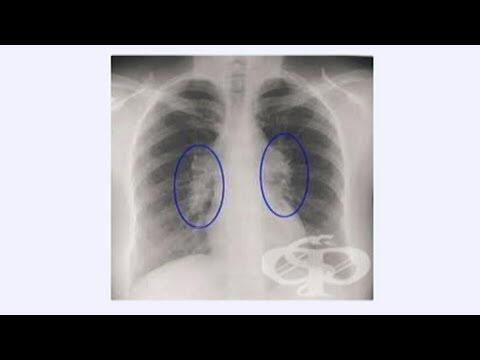

Саркоидоза - диагностика, профилактика и лечение